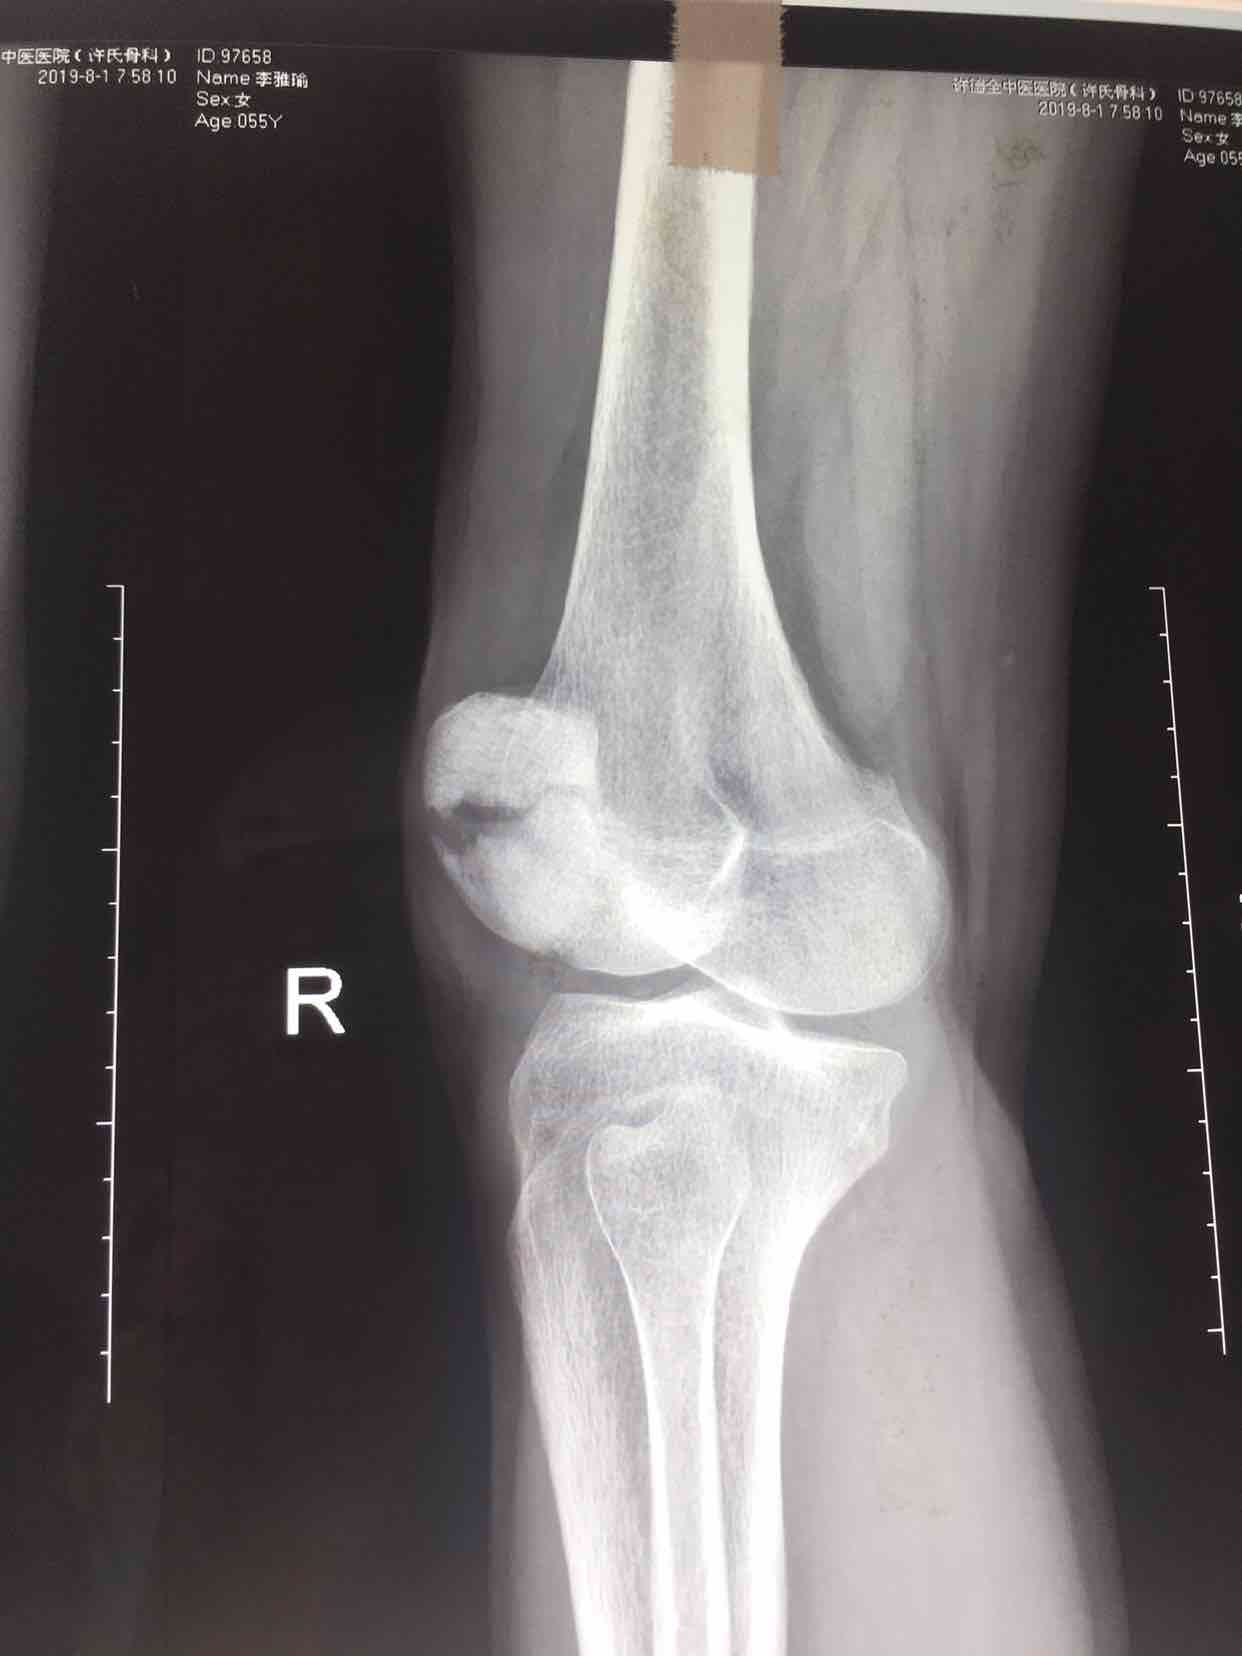

髌骨骨折(髌骨爪➕克氏针应用)

骨折 髌骨骨折

摔伤后右膝部肿痛,活动受限1小时入院。既往身体健康,无特殊不良嗜好。

生命体征平稳,心肺复未见异常。右膝部肿胀明显,皮色微红,皮温高,可及骨檫音及骨折断端,压痛明显,伸膝关节受限,末梢血运感觉正常。

诊断右髌骨骨折在腰麻下行切复内固定术,术后抗炎,消肿等处理。